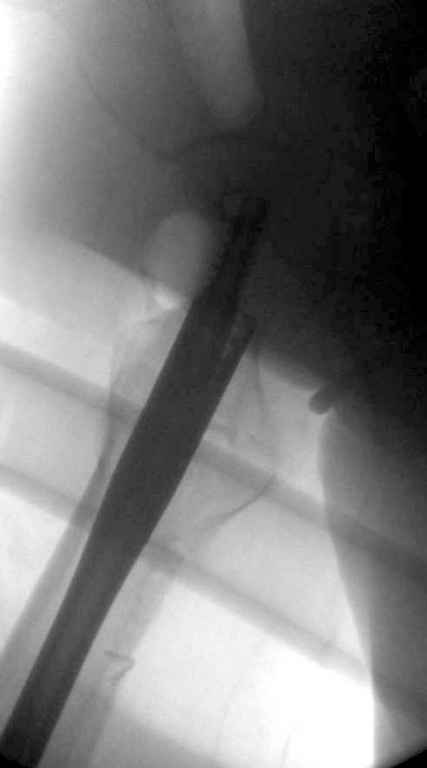

Вашему вниманию представляется похожий случай, пациентке 70, осложнился в течение одного месяца после операции. Ревизия с заменой сустава, кабельная фиксация на трохантер. При установке в дистальном диафизе обнаружен тонкий кортикальный слой и сделана профилактика от возможного перелома аллографтом.